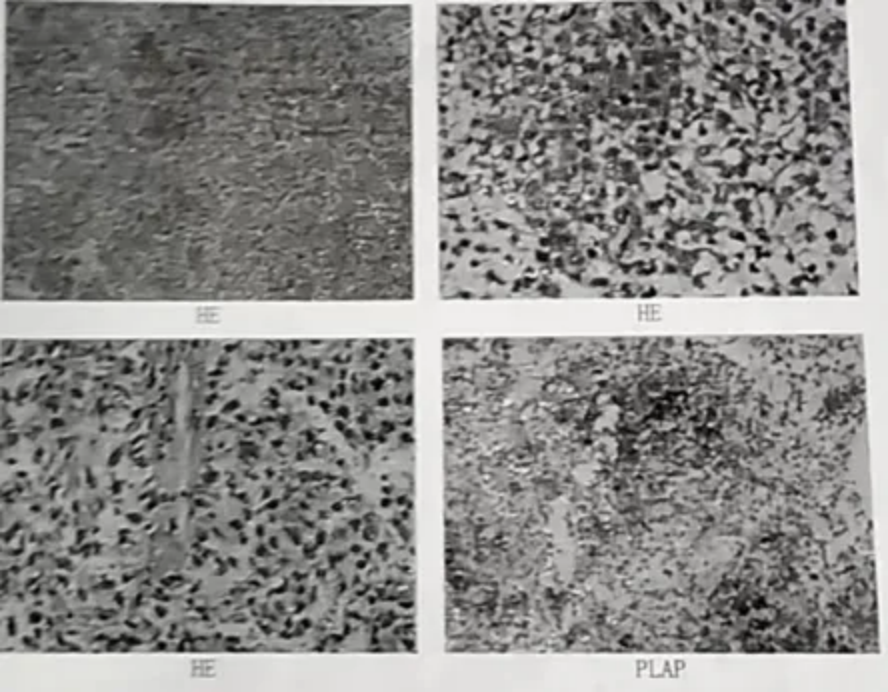

图2 术后病理

免疫组化结果:EMA(-),PR(-),Vimentin(+),P53(+),S-100(-),Syn(-),NSE(部分+),CD99(-),GFAP(-),Ki-67(+,60%),CD30(-),SALL-4(+),Glypican3(-),PLAP(+),CD117(+),Inhibin-α(-)。